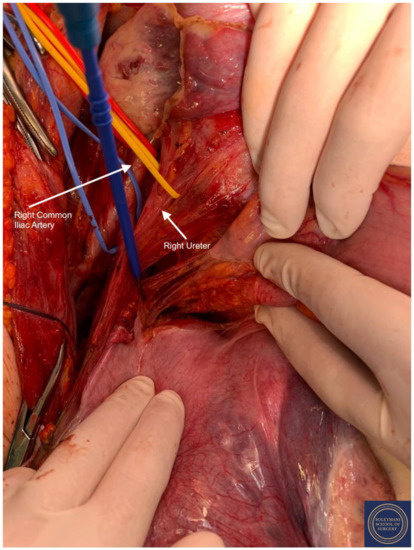

Approach to Radical Hysterectomy for Cervical Cancer in Pregnancy: Surgical Pathway and Ethical Considerations

by Rocco Guerrisi, Sarah Louise Smyth, Lamiese Ismail, Amanda Horne, Federico Ferrari and Hooman Soleymani majd

J. Clin. Med. 2022, 11(24), 7352; https://doi.org/10.3390/jcm11247352 - 10 Dec 2022

Introduction. Cervical cancer is currently the fourth most common cancer in women and in the poorest countries this neoplasia still represents a widespread and potentially lethal disease. We present a rare case of cervical cancer in pregnancy, analyzing the historical changes behind the procedure of radical hysterectomy for cervical cancer and discussing variations in surgical techniques and anatomical definitions that have since been proposed. Results. We present the case of a 33-year-old patient who attended with vaginal bleeding in the second trimester of pregnancy. Examination revealed an abnormal looking cervix, with investigations concluding stage IIb squamous cell carcinoma. Following extensive discussion regarding management options, the patient went on to have a peripartum foetocidal type III nerve sparing radical Wertheim hysterectomy at 18 weeks gestation with conservation and transposition of the ovaries above the level of the pelvic brim. The patient recovered well without significant morbidity and received further input from fertility and psychological medical teams in addition to adjuvant treatment within the department of clinical oncology. Discussion. This case represents several elements of great interest and learning. Notably, we highlight this both due to the surgical challenges that a gravid uterus presents in the execution of a radical hysterectomy; and regarding the compassionate care demonstrated by the team - not only in supporting the patient and her partner in a period of profound turmoil in terms of the management of their cancer diagnosis and unborn child, but also regarding the uncertainty in consideration of the oncological and fertility related outcomes. Conclusion. This manuscript adds to the growing literature on the appropriate use of radical surgery for cervical cancer, more specifically during pregnancy and in consideration of such ethical dilemma, where management guidelines do not exist to aid clinicians further in their provision of treatment. Full article